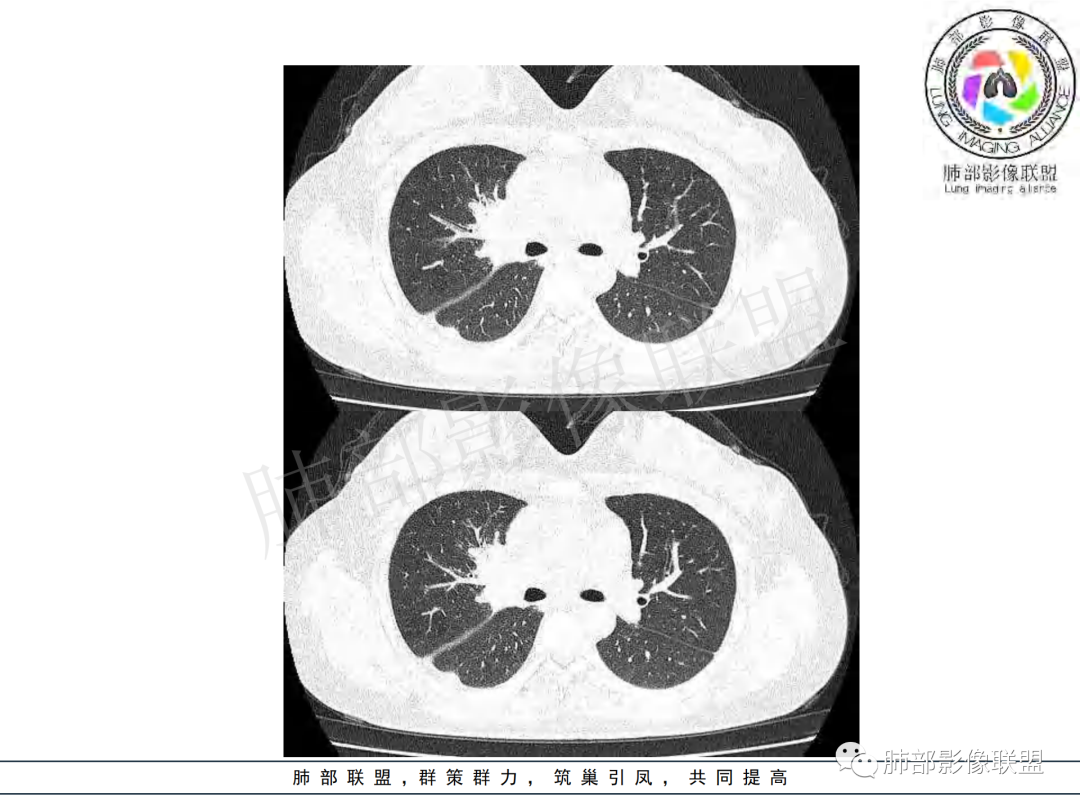

年龄和病史比较符合结核,但是中叶支气管好像堵塞了,管腔有新生物,恶性肿瘤也不能排除,做一个支气管镜应该能确诊

支气管腔内有占位,肺门区病灶和胸膜结节明显强化,淋巴结环状强化为主,部分明显强化,年轻女性,首先考虑结核,鉴别腺癌

女性,20岁。高热、畏寒。右肺上叶近肺门区不规则肿块,周围斑点、片小结节影伴肿大淋巴结,肿块包绕并突入右主支气管腔内,增强后肿块不均匀强化,淋巴结环形强化中心低密度,考虑结核。

本例患者,年轻女性,慢性病程,多次抗感染治疗效果不佳,实验室检查示白细胞及中性粒细胞不高,不支持普通细菌感染,虽然肺泡灌洗液X-Pert检测阴性,结合患者胸部CT结核感染亦不能排除,胸部CT主要表现为右侧肺门及纵隔淋巴结肿大,仔细观察不难发现右中间支气管内新生物凸向管腔内,增强扫描,右肺门(10R)及纵隔淋巴结(2R,4R)明显不均匀强化,内部呈不规则低密度无强化区,被周边高强化区包绕(环形强化)的特点,首先应当想到纵隔淋巴结结核诊断。淋巴结分布亦不符合肺部恶性肿瘤迁徙途径。